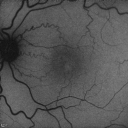

FUNDUS AUTO FLUORESCENCE: The fundus auto fluorescence images show some loss of macular pigment in the temporal region of both eyes with telangiectasis to the vessels.